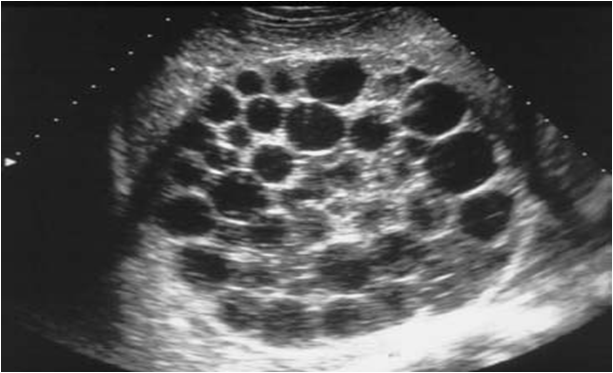

Hydatid liver cysts are caused by infection from tapeworm Echinococcus granulosus or, less commonly, Echinococcus multilocularis. These cysts are most commonly found in the right lobe of the liver. Small cysts are usually asymptomatic but larger cysts may cause pain in the right upper abdominal quadrant. They may rupture into the peritoneal cavity, causing fatal anaphylactic shock. Treatment includes surgical resection. Mebendazole should be started after surgery.